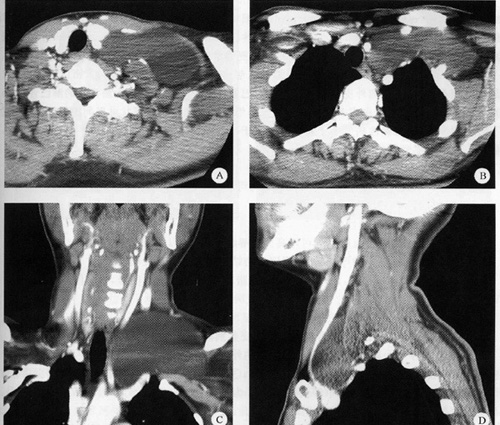

标题: CT17731病理:淋巴管瘤 [打印本页]

标题: CT17731病理:淋巴管瘤

各位战友水平真高,病理结果是淋巴管瘤,此病例唯一不符合的是患者的年龄,淋巴管瘤多好发于小孩,术前虽然我们也考虑淋巴管瘤可能性大,但心里总还是有点怀疑,摘录书上的一例典型病例,大家共同复习一下